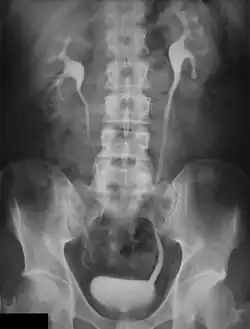

An intravenous pyelogram (IVP), also called an intravenous urogram (IVU), is a radiological procedure used to visualize abnormalities of the urinary system, including the kidneys, ureters, and bladder. Unlike a kidneys, ureters, and bladder x-ray (KUB), which is a plain (that is, noncontrast) radiograph, an IVP uses contrast to highlight the urinary tract.

An injection of X-ray contrast medium is given to a patient via a needle or cannula into the vein,[7] typically in the antecubital fossa of the arm. The contrast is excreted or removed from the bloodstream via the kidneys, and the contrast media becomes visible on X-rays almost immediately after injection. X-rays are taken at specific time intervals to capture the contrast as it travels through the different parts of the urinary system.[7] At the end of the test, a person is asked to pass urine and a final X-ray is taken.[7]

Normal appearances

Immediately after the contrast is administered, it appears on an X-ray as a 'renal blush'. This is the contrast being filtered through the cortex. At an interval of 3 minutes, the renal blush is still evident (to a lesser extent) but the calyces and renal pelvis are now visible. At 9 to 13 minutes the contrast begins to empty into the ureters and travel to the bladder which has now begun to fill. To visualize the bladder correctly, a post micturition X-ray is taken, so that the bulk of the contrast (which can mask a pathology) is emptied.